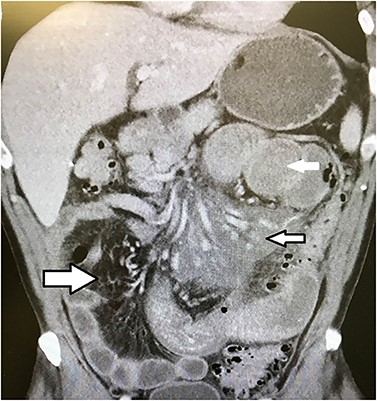

The entire excised specimen showing all of the enlarged necrotic lymph nodes and ischemic bowel.

Emergent laparotomy was performed. He was found to have multiple enlarged necrotic mesenteric lymph nodes with purulent material draining from the capsule of the nodes (Fig. 2). Several large areas of the proximal mesenteric fat were necrotic with vascular occlusion and thrombosis, which was causing ischemia of the proximal jejunum. The proximal jejunum was very dusky and dilated, while the distal small bowel and colon was normal. The duodenum was spared. The necrotic fat and lymph nodes extended down to and around the superior mesenteric artery, where multiple side branches off the artery showed no blood flow by Doppler examination. The ischemic small bowel was excised along with its mesentery down to the superior mesenteric artery, to include the excision of the necrotic lymph nodes (Fig. 3). The bowel was left in discontinuity, and the patient was taken to the intensive care unit with a temporary abdominal closure. He was taken back to the operating theatre the next day for a second look, and the remaining small bowel was found to be viable and healthy. A duodenal to distal jejunal anastomosis was performed and the abdomen was closed.